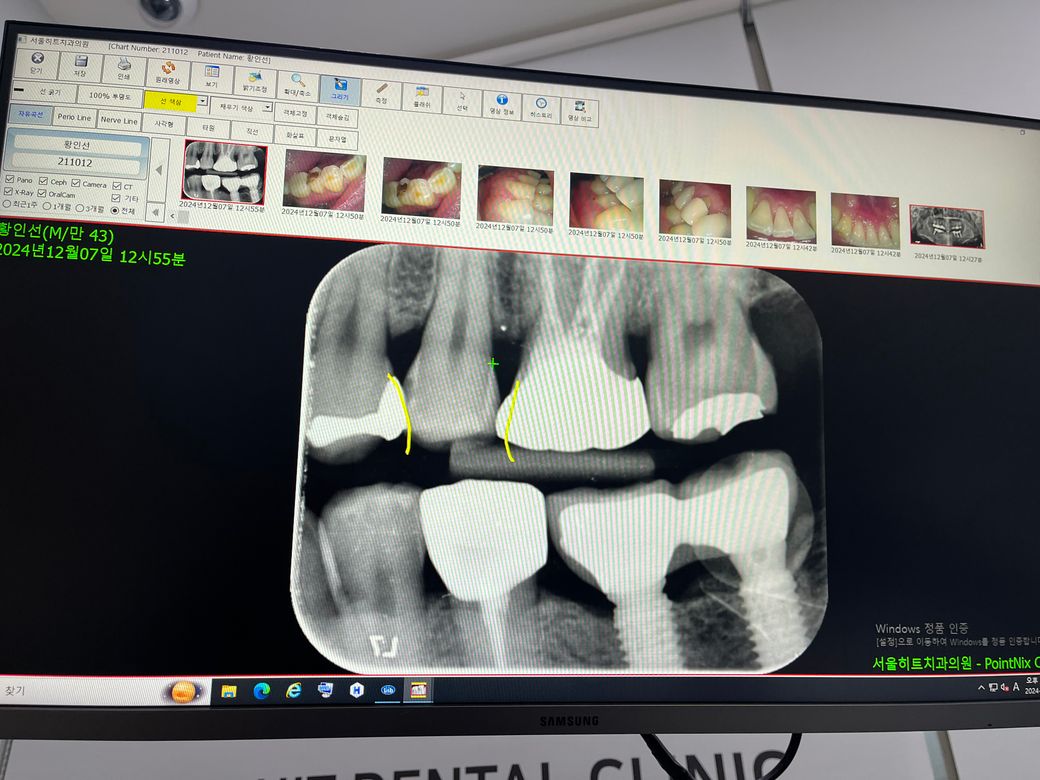

노란색 표시된 사이의 이가 옆쪽이 썪었다고 해서 크라운 치료해야한다고 합니다.

x-ray상에서 옆면에 충치가 관찰이 됩니다. 크기는 아주 크지 않으며 신경관과도 거리가 있어 보입니다.

일단 신경치료는 필요하지 않을 것으로 판단됩니다.

충치를 해결하는 방법으로는

1. 레진치료 - 옆면 충치인 경우에도 레진으로 치료하는 치과들이 늘어나고 있는 추세입니다.

2. 인레이치료 - 옆면 충치일 경우 가장 스탠다드하게 선택되는 치료법입니다. 저도 추천드립니다.

3. 크라운 치료 - 양쪽 옆면 충치일 경우 선택하는 경우가 있으나, 꼭 필요한 경우가 아니라면 치아 삭제량이 많기에 신중히 선택해야 합니다.

가 있겠습니다.